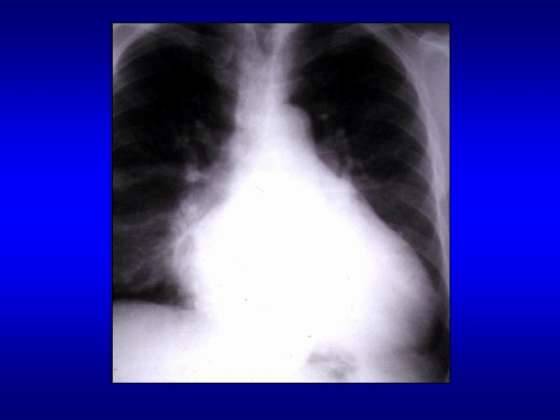

Radiografia cardiopulmonara

Semnele radiologice sunt diferite in raport cu forma de insuficienta mitrala acuta sau cronica

In insuficienta mitrala acuta se constata:

- atriul stang normal sau mic;

- staza pulmonara (hil stufos, linii Kerley)

In insuficienta mitrala cronica se constata:

- atriul stang enorm enorm;

- ventricul stang marit, ulterior ventricul drept marit datorita supraincarcarii

sistolice;

- indice cardiotoracic marit peste 0,5;

- calcificari de inel mitral;

- hiluri si circulatie pulmonara incarcate ( HTP venoasa, linii Kerley);

- dilatarea arterei pulmonare.